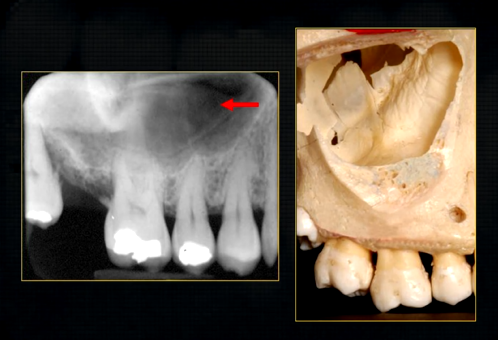

mental foramen - black radiolucency - near 1st and 2nd premolars

sockets of the teeth are represented by thin, white, opaque lines → ‘ lamina dura’

dense, white, radiopaque line → dense bone of mylohyoid ridge

underneath mylohyoid ridge - looks more radiolucent → this is due to the lingual indentation of submandibular fossa

dense cortical bone of the lower border

radiolucent shadow created by the lingual pit